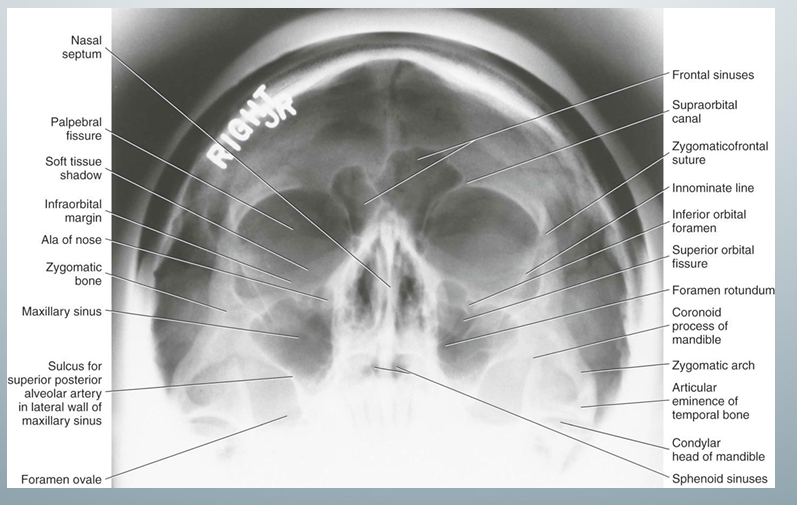

Waters view

-used to evaluate maxillary sinuses (can see without obstruction)

Waters view- uses, image receptor placement, pt position, central x-ray position, notes

how to take waters view

-image receptor perpendicular to pt’s midsagittal plane

-pt faces image receptor and tilts head upward so the canthomeatal line forms a 37 degree angle with the image receptor

-head tilt position similar to head tilt when drinking water

-central x-ray beam positioned centered over the maxillary sinuses